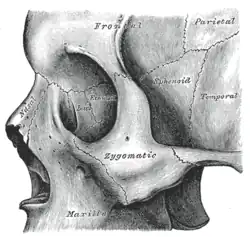

Slzní kost je označena „lac.“ a nachází se na vnitřní straně očního důlku | |

Vizualizace slzní kosti na lebce

Vizualizace slzní kosti na lebce